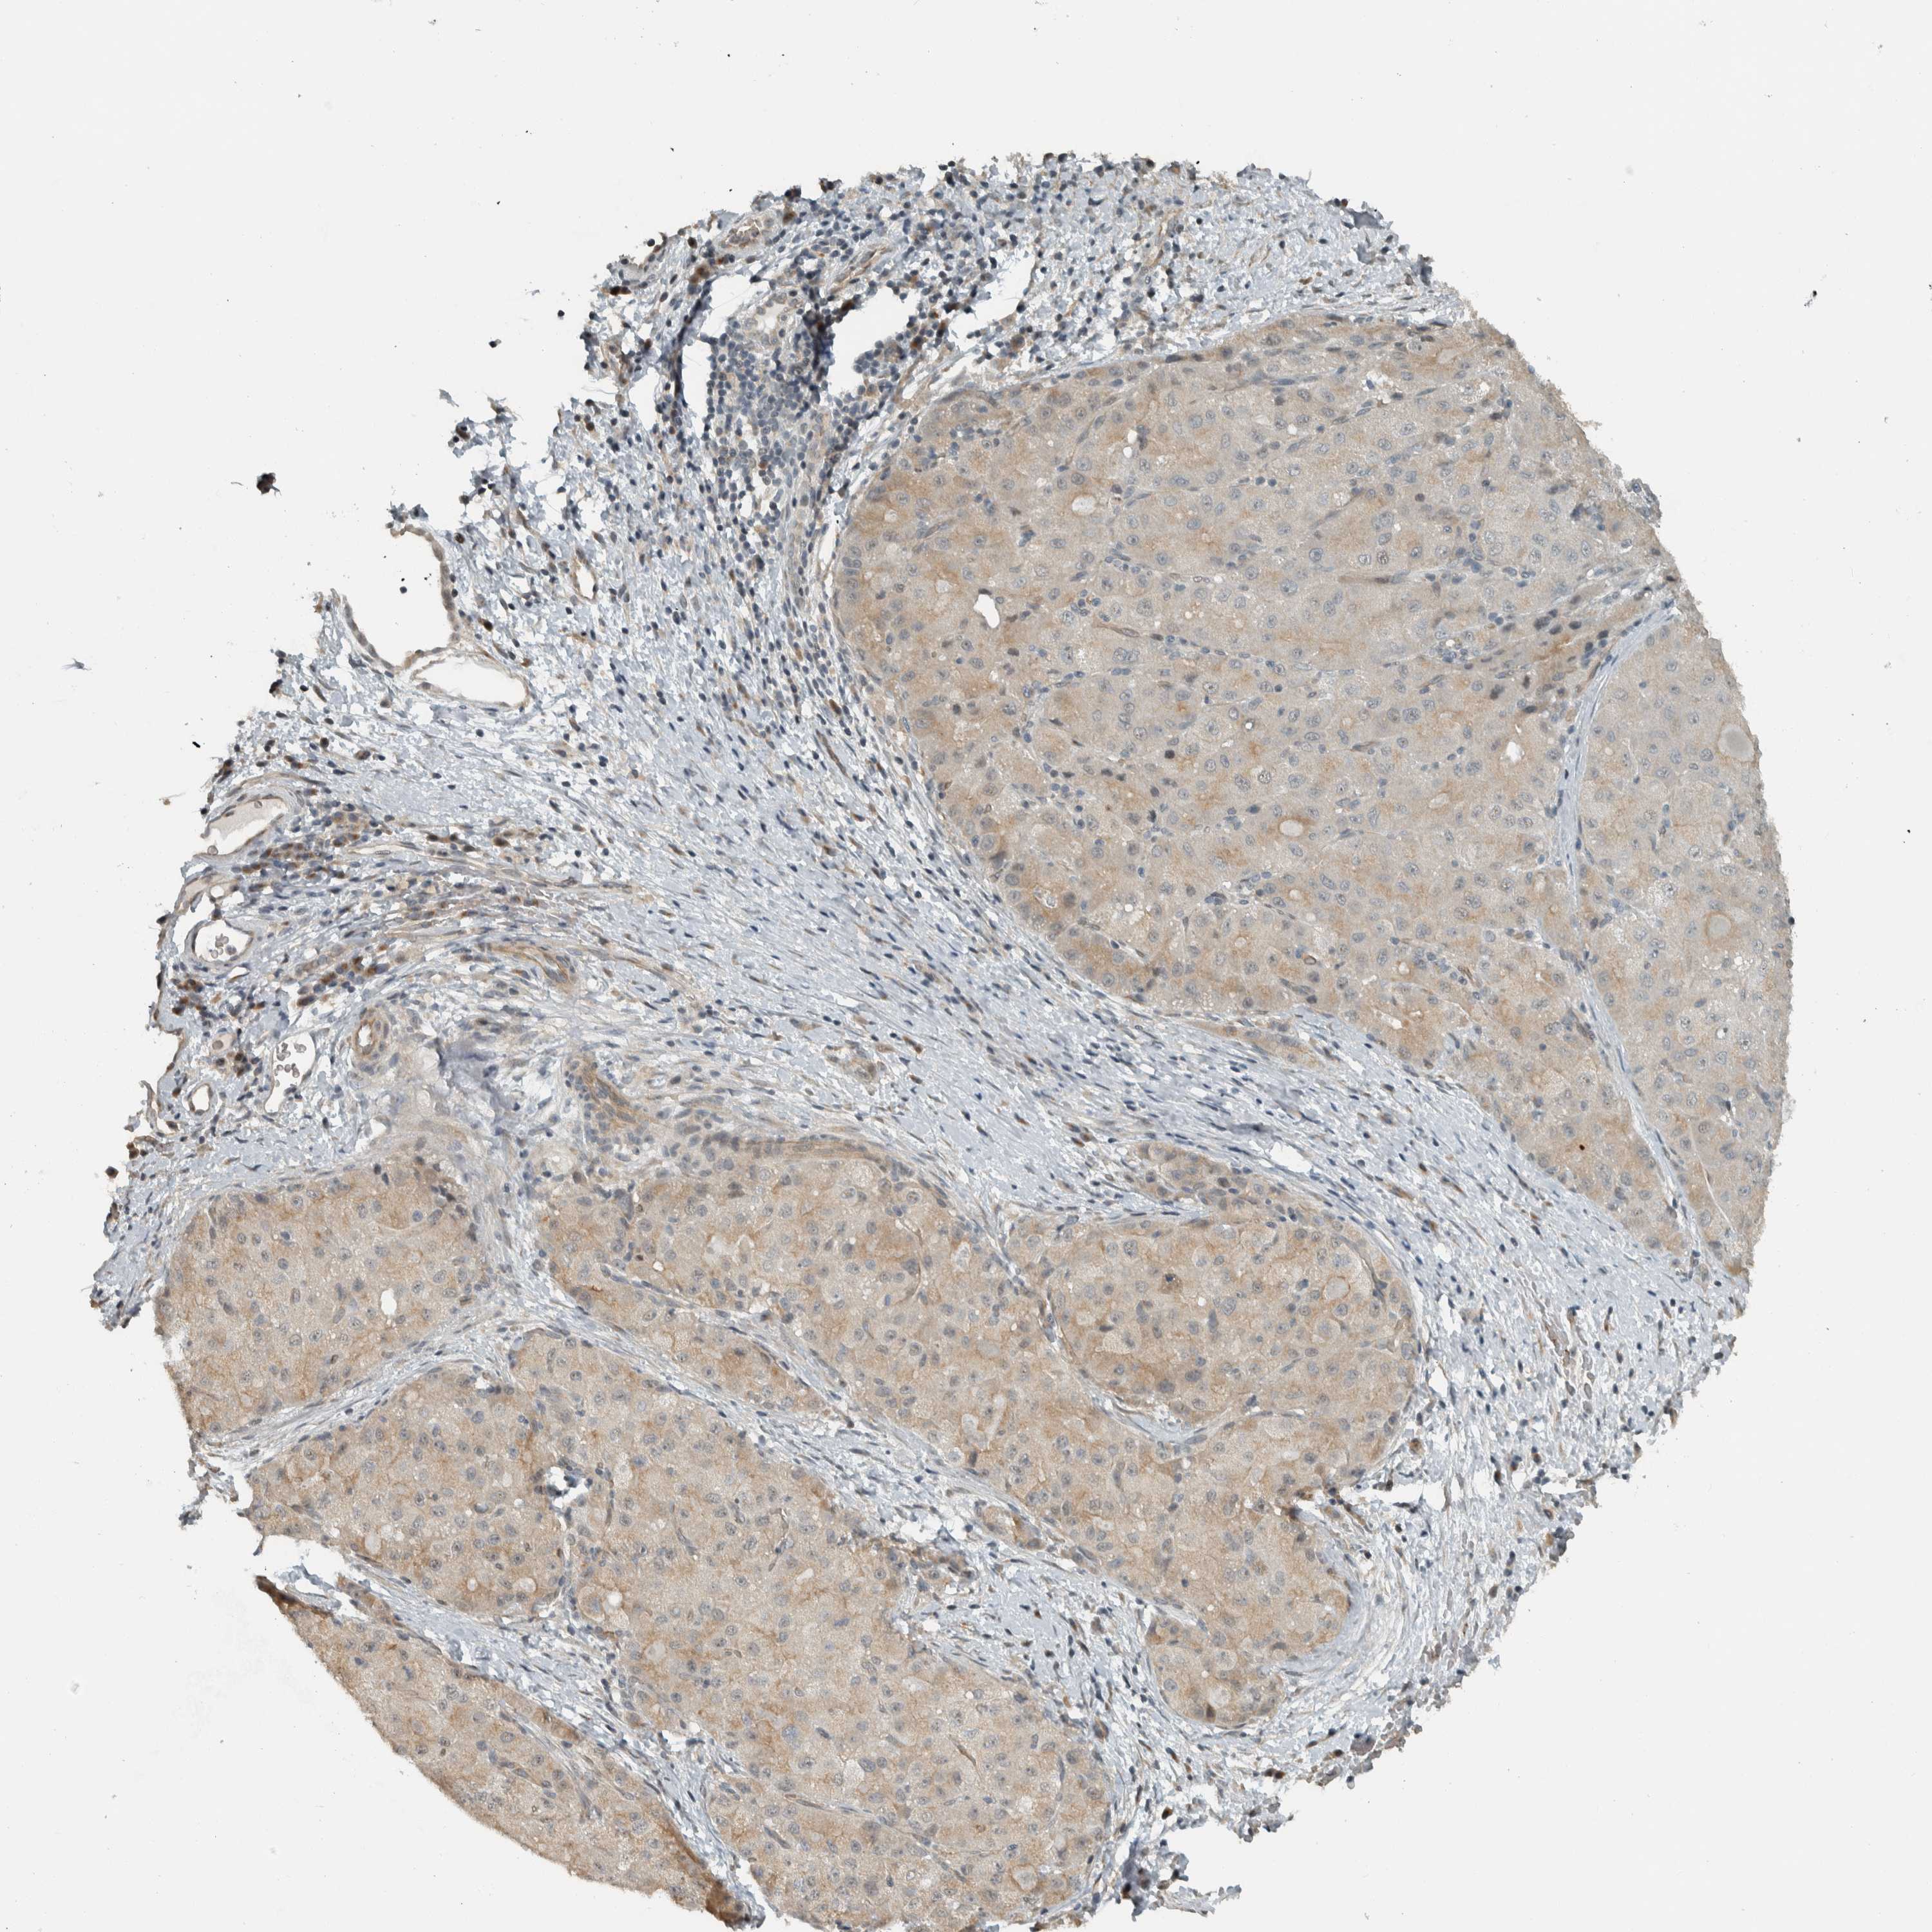

LIVER CANCER - Protein expressioni

A mouse-over function shows sample information and annotation data. Click on an image to view it in a full screen mode. Samples can be filtered based on level of antibody staining by selecting one or several of the following categories: high, medium, low and not detected. The assay and annotation is described here.

Note that samples used for immunohistochemistry by the Human Protein Atlas do not correspond to samples in the TCGA dataset.

Antibody stainingi

Antibody staining in the annotated cell types in the current human tissue is reported as not detected, low, medium, or high, based on conventional immunohistochemistry profiling in selected tissues. This score is based on the combination of the staining intensity and fraction of stained cells.

Each image is clickable and will lead to virtual microscopy that enables deeper exploration of all samples and also displays staining intensity scores, fraction scores and subcellular localization as well as patient and tissue information for each sample.

Antibody HPA011389

Staining

High

Medium

Low

Not detected

Intensity

Strong

Moderate

Weak

Negative

Quantity

>75%

75%-25%

<25%

None

Location

Nuclear

Cytoplasmic/membranous

Cytoplasmic/membranous,nuclear

Cholangiocarcinoma

Carcinoma, Hepatocellular, NOS